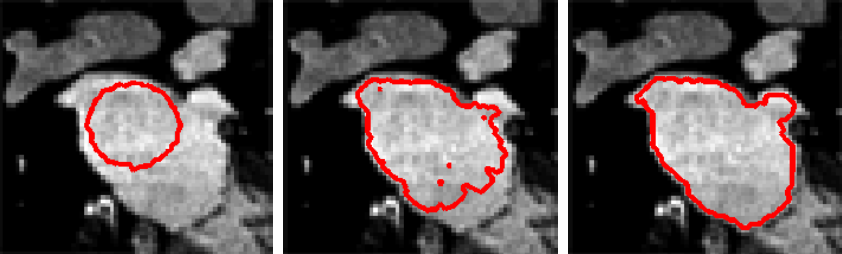

概念五:基于曲线演化的图像分割

如果用基于曲线演化的图像分割方法,就是在要分割的图片上,先随便绘制一条曲线,然后让这条曲线演变成我们想要的曲线,分割就完成了。

比如先在目标上随意画一个圈(左图),然后曲线每个点加上运动方向和速度进行演变(中图),最后各点速度都减小到 0,就达到了最终的分割结果(右图)。

要达到上图效果的具体做法: